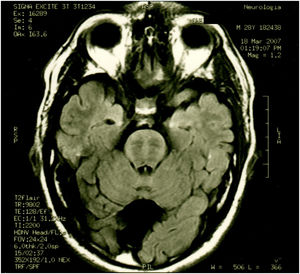

ResultsCase 1 is a 50-year-old male born from a non-consanguineous marriage in Mexico City (Fig. 1A). At age 5, he developed progressive ataxia, dysmetria, cerebellar tremor, and slurred speech. The initial neurological examination revealed bilateral gaze-evoked nystagmus, preserved strength 5/5 except for distal lower limbs (2/5), absent reflexes in all extremities, increased muscle tone in lower limbs, absent Babinski sign, and decreased vibration sensation in lower extremities. Clinical findings are summarized in Table 1. Pes cavus and hammertoes were evident on the last examination at age 47 (Fig. 2); gait was ataxic and only possible with crutches. Brain MRI revealed severe cerebellar and cervical spine atrophy (Fig. 3).

| Patient 1 (Family 1) | M | 47 | 5 | Ataxia, slurred speech, nystagmus, spasticity and decreased vibration sensation in lower extremities, pes cavus and hammertoes | Severe cerebellar and cervical spine atrophy Fig. 3 |